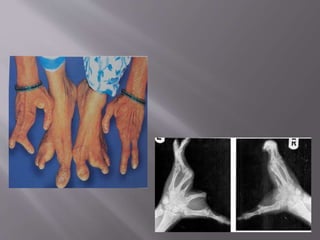

 Lobster claw deformity: Split hand & foot – MC

 3rd & 4th Digits - MC

 Tetramelic involvement –MC

X – Ray of deformed hand show absence or

hypoplasia of Meta carpals & Metatarsals